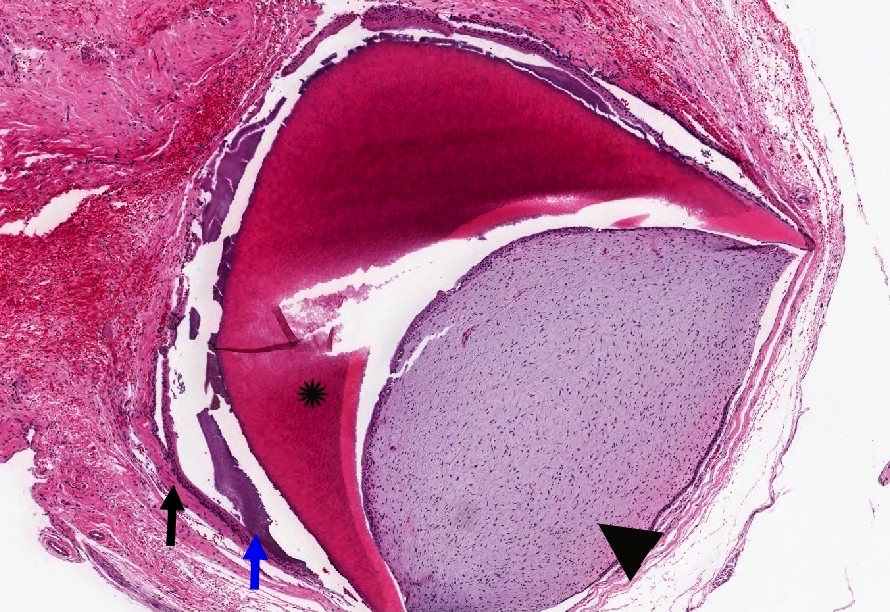

Microscopic (histologic) description

- General:

- Can have scant or occasional ghost cell formation, can cause confusion with COC (CCOT / Gorlin cyst) Calcifying cystic odontogenic tumor (CCOT)

- Odontoma can also occur as a component of COC (about 20% of COC associated with odontoma)

- Odontoma is composed of dental hard tissues; dentin and enamel

- Bone is not a dental hard tissue

- Compound:

- Histologically similar to the layering of normal tooth in the relation of dentin, enamel matrix and pulp

- Complex:

- More disorganized or haphazard arrangement of pulpal tissues, enamel or dentin

Microscopic (histologic) images